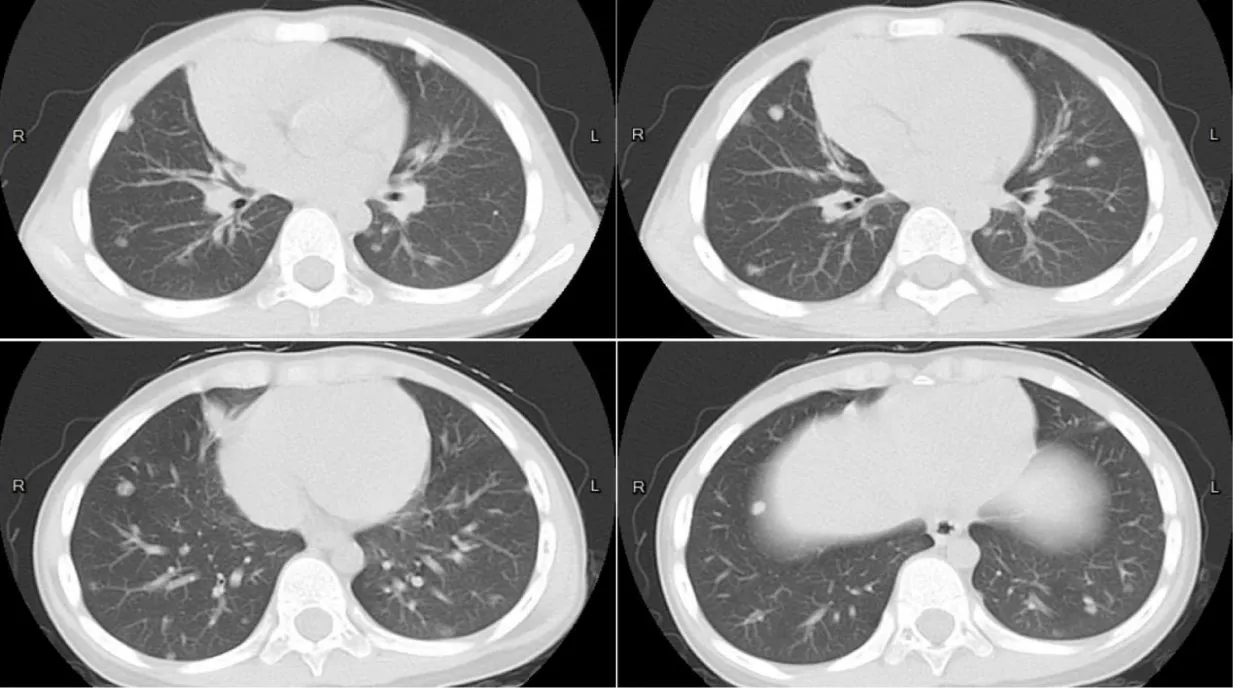

Lumbar puncture under general anesthesia showed elevated CSF pressure (>330 mm H2O), lymphocytic pleocytosis (7×10⁶/L, 89% lymphocytes), and elevated protein (634 mg/L), though glucose levels were normal (2.7 mmol/L). Next-Generation Sequencing (NGS) of CSF identified Entamoeba dispar (447 reads), while extensive serological tests for bacterial, fungal, and parasitic pathogens (including tuberculosis, toxoplasmosis, and neurocysticercosis) were negative. Chest CT revealed subpleural and mid-lung field nodules (Figure 4), suggesting possible pulmonary involvement. The patient received three 10-day courses of metronidazole (50 mg/kg/day) over five months, with intervals of 1-2 months between courses. Follow-up MRI of 4 years showed progressive resolution of brain lesions, including absorption of the cysts, reduction of lesion size, decreased enhancement and alleviation of the perilesional edema (Figures 5a-e).